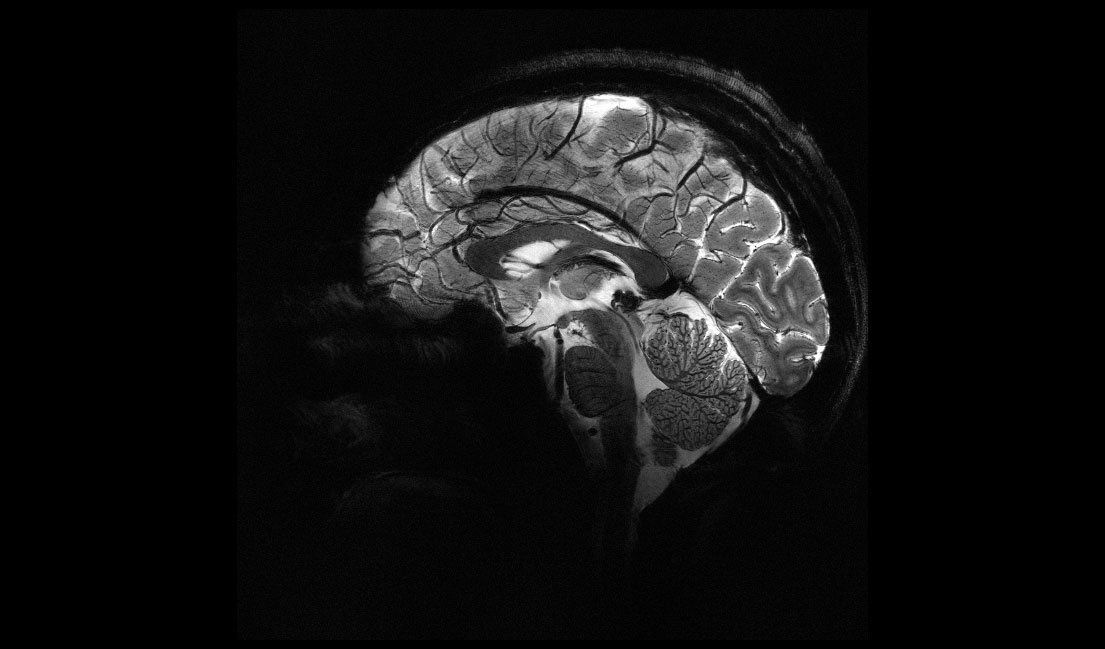

Das CEA veröffentlicht eine Reihe von In-vivo-Bildern des menschlichen Gehirns, die mit dem MRT-Gerät "Iseult" und seiner unübertroffenen Magnetfeldstärke von 11,7 Tesla aufgenommen wurden. Dieser Erfolg ist das Ergebnis von mehr als 20 Jahren Forschung und Entwicklung im Rahmen des Iseult-Projekts, dessen Hauptziel es war, das leistungsstärkste MRT-Gerät der Welt zu entwickeln und zu bauen. Das Ziel ist es, gesunde und kranke menschliche Gehirne mit einer noch nie dagewesenen Auflösung zu untersuchen. In der Alzheimer- und Parkinson-Forschung könnte dies zum Beispiel neue Informationen über die Neurodegeneration in verschiedenen Hirnregionen liefern und zu einer besseren Diagnose beitragen.

MRT-Aufnahme des Gehirns mit derselben Auflösung bei unterschiedlichen Magnetfeldstärken. Bei 3 Tesla und bei 7 Tesla sind Präzision und Schärfe geringer. Bei 11,7 Tesla liefert der Scan mehr Signale und größere Kontraste zwischen biologischen Geweben, was eine detailliertere Untersuchung des Gehirns ermöglicht.